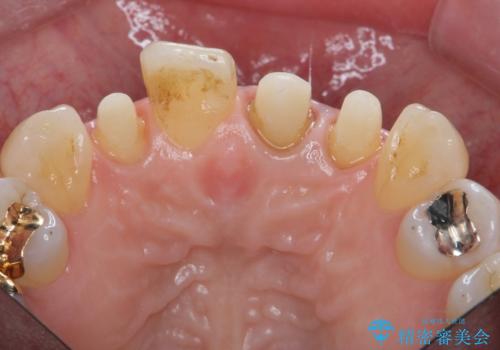

- 前歯のクラウンの歯肉の位置が年々変化し、歯ぐきのフチが黒くなってしまった、綺麗にしたいと希望されて来院されました。

装着されているセラミッククラウンを除去したのち、現在の歯ぐきのラインにしっかりと合う精度の高いオールセラミッククラウンを作製していきます。